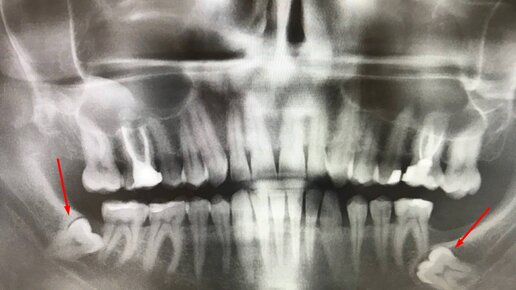

Удаление зубов мудрости — не самая сложная операция в стоматологической практике, но для многих людей она кажется страшной и вызывает массу вопросов. Стоматолог «Белой радуги» Журов Илья Владимирович рассказывает, как должна проходить процедура удаления зубов мудрости, чтобы у пациента не было осложнений, а ее последствия не привели к проблемам с зубами в будущем. В статье он ответит на вопросы: Этап 1. Сбор анамнеза и осмотр перед удалением зубов мудрости Когда у человека болит зуб мудрости, он...